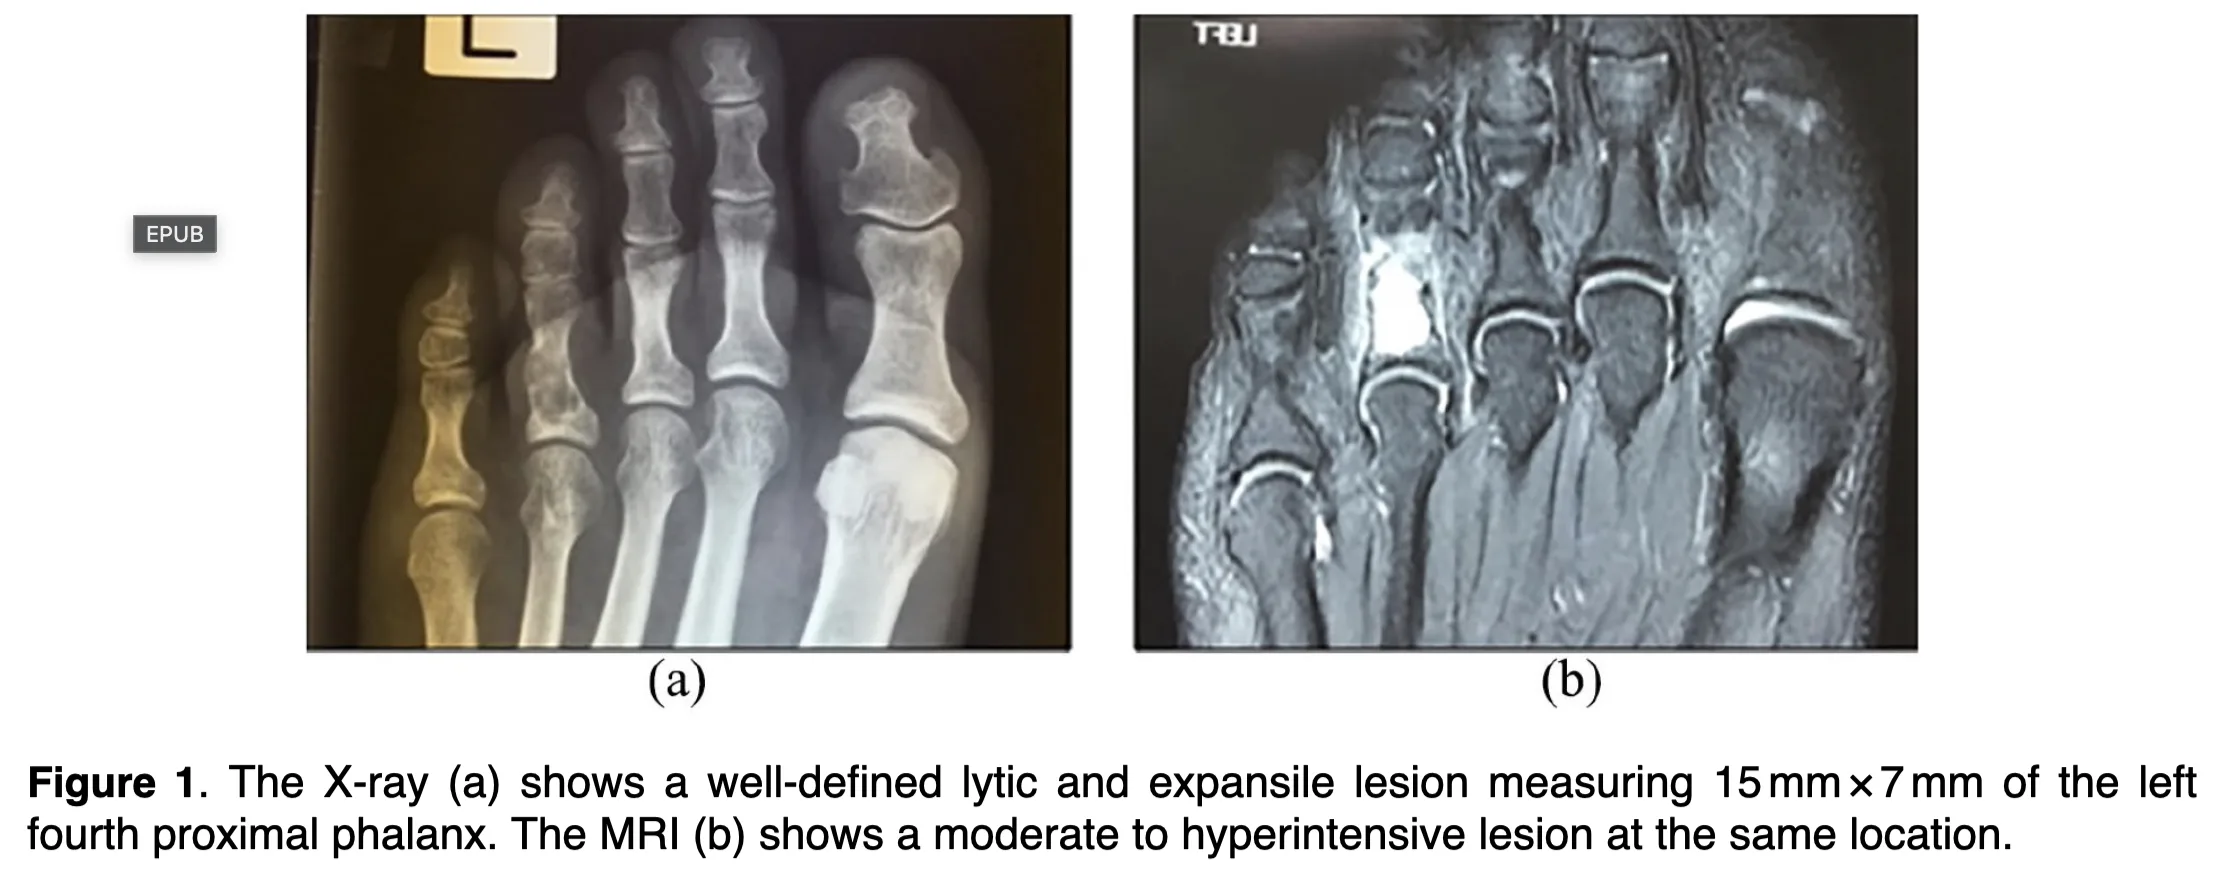

X線写真では, 腫瘍による骨破壊によって骨の中が透けるように黒っぽく写っていて, 内部に斑状の白い石灰化陰影を認めます.

MRI T2強調画像では, 水分含量の多い軟骨基質を反映して腫瘍部が白く描出されています.

1人は, 中高年の第4足趾基節骨の骨腫瘍が疑われた患者さんで, X線写真の所見から内軟骨腫が疑われました.

MRIでは, 腫瘤部野中に血液の塊(血栓)(図中の→)を認めます.